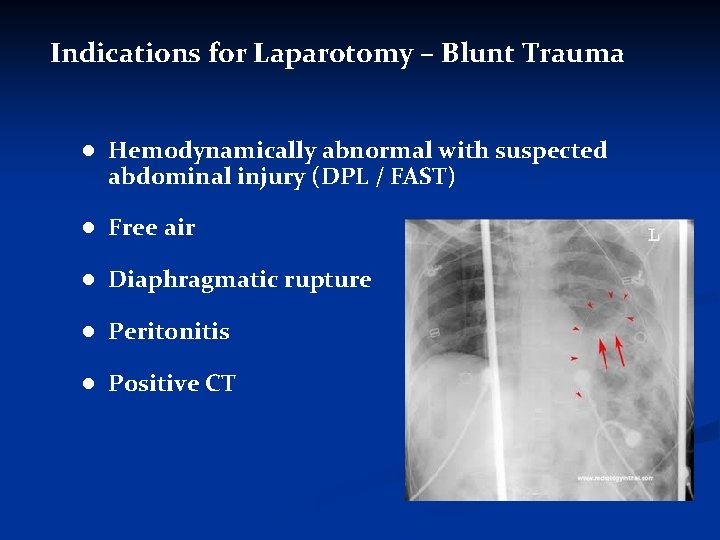

Indications for Laparotomy – Blunt Trauma ● Hemodynamically abnormal with suspected abdominal injury (DPL / FAST) ● Free air ● Diaphragmatic rupture ● Peritonitis ● Positive CT